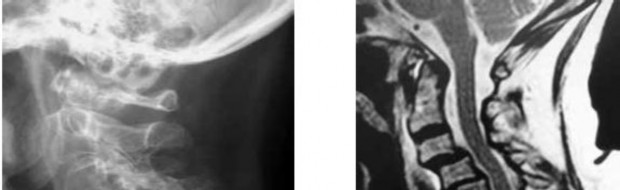

A 60-year-old male of East Asian descent presents with progressive clumsiness in his hands and an unsteady gait.

Lateral cervical radiographs reveal a continuous, dense radiopaque stripe immediately posterior to the vertebral bodies from C3 to C6. What is the most likely diagnosis?

A 60-year-old Japanese male presents with progressive clumsiness of his hands, difficulty walking, and hyperreflexia in both upper and lower extremities. Lateral cervical radiograph reveals dense ossification extending vertically along the posterior aspect of the C3 to C6 vertebral bodies. Which surgical approach is generally preferred if the canal occupying ratio is 60% and cervical alignment is lordotic?